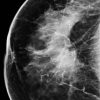

Ung thư vú

» Thông tin: Nữ giới – 76 tuổi.

» Lâm sàng: Khối tuyến vú.